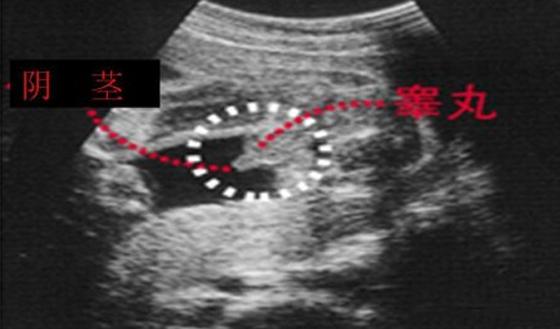

男宝宝B超图:

男宝宝的B超图上其实是能看到小鸡鸡的,图片的红圈处就是。这张图片上的小鸡鸡非常清晰,医生很厉害,她取的那个角度就是宝宝的屁股正下方,看的特清楚。

“凸出的东西” 是他的标记: 你们看到圆圆的是DANDAN,如果看到圆圆的加小肠的就是全部JJ。